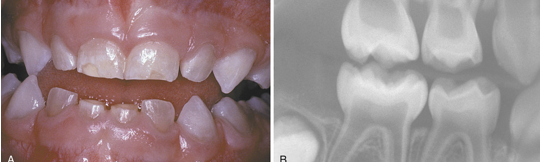

osteogenesis imperfecta as characterized by brown translucence of teeth and radiographs showing shell teeth with thin dentin and enamel of normal thickness